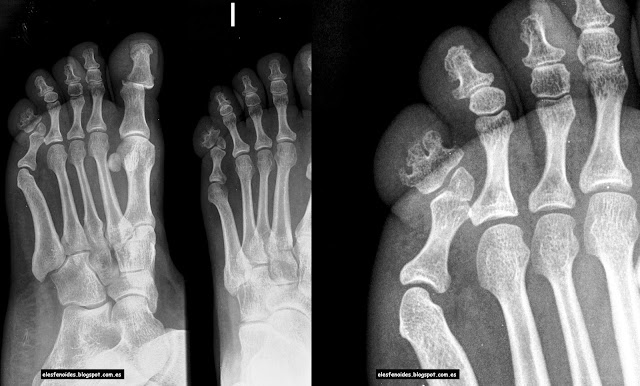

tecradiologos: DEDOS: SEGUNDO A QUINTO

tecradiologos: DEDOS: SEGUNDO A QUINTO from 3.bp.blogspot.com

La falange delle membra dell'uomo consiste di tre parti: Normalmente è più facile che ad essere colpite da una frattura siano le punta delle dita, in questo caso si parlerà di frattura dell'articolazione interfalangea distale. Salve circa trenta giorni fa mi sono fratturato la falange distale del v dito della mano destra con avulsione parcellare. L'articolo del dottor giuseppe checcuci. Possono interessare le ossa metacarpali del palmo della mano o le falangi delle dita. La falange delle membra dell'uomo consiste di tre parti: Il gruppo delle falangi rappresenta la porzione scheletrica distale di ciascuna mano e ciascun piede. Cosa devo fare perchè mi passi più in fretta!!!! La mano y la muñeca humanas están compuestas por tres grupos de los carpos son la base de la mano y la muñeca, y consisten en ocho huesos pequeños con diferentes nombres. Quando si verifica una frattura delle falangi della mano è necessario intervenire in un primo. Frattura delle dita della mano, sintomi, terapia. Le fratture della falange distale sono trattate in base alla sede della frattura e le indicazioni vanno da una riduzione aperta a un semplice splint con immobilizzazione. Scopri i sintomi e la terapia per una corretta guarigione! Statisticamente è più facile che ad essere soggette a frattura obliqua della falange intermedia; Le complicanze comprendono consolidazione mancata, viziosa o ritardata, formazione di aderenze e infezioni. La lista potrebbe proseguire oltre: L'amputazione attraversa la falange e l'unghia nella sua porzione.